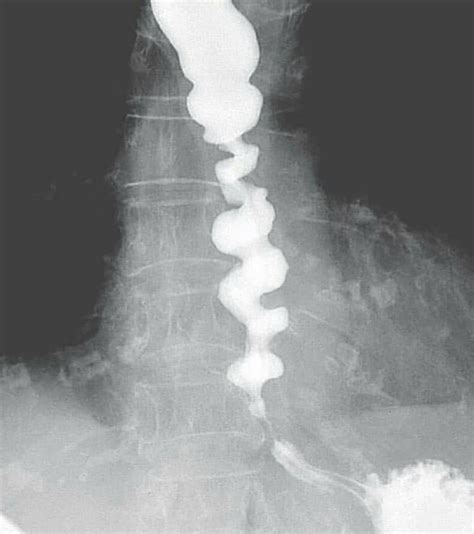

Okay, so what exactly is a spasm? In simple terms, a spasm is an involuntary and sudden contraction of a muscle or group of muscles. These contractions can range from mild twitches to severe pain, and they can happen in any muscle in your body. Think of it like this: your muscles are supposed to contract and relax smoothly, but during a spasm, they contract forcefully and refuse to relax, causing discomfort or pain. Spasms are incredibly common, and most of us will experience one at some point in our lives. They can occur for various reasons, from simple dehydration to more complex neurological conditions. Understanding the nature of a spasm is the first step in effectively managing and preventing them.

Muscle spasms can vary greatly in intensity and duration. Some might feel like a slight twitch that you barely notice, while others can be intensely painful and last for several minutes. The location of the spasm can also differ, affecting different parts of the body such as the legs, back, neck, or even smaller muscles like those in your eyelids. These variations are crucial because they can indicate different underlying causes and require different approaches for relief. Recognizing the type and pattern of your spasms can provide valuable clues for healthcare professionals to diagnose and treat the root cause effectively. Think about when the spasms occur – is it after exercise, during sleep, or seemingly at random? Keeping track of these details can help you and your doctor get to the bottom of what’s going on.